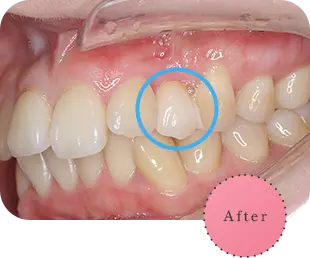

主訴

上の前歯が長くて気になる

治療期間

9か月

治療費

30万円

治療内容

右上1番を小矯正治療にて歯茎を増やし、右上1番と左上1番をセラミッククラウンにて修復

治療のリスク

咬み合わせによっては、セラミックが欠ける可能性があります。